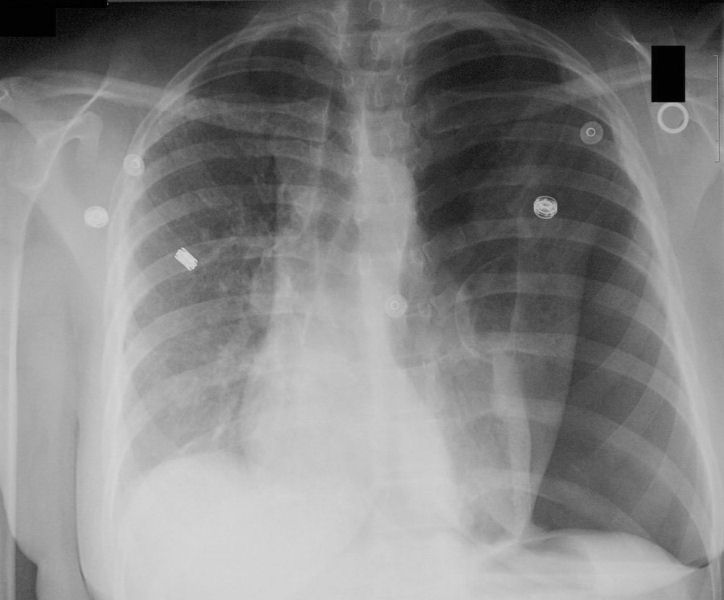

back pneumothorax

Source: Pneumothorax CXR.jpg